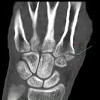

Рентгенография мягких тканей подмышечной области

Рентгенография мягких тканей в подмышечной области. Рентгеновский метод подмышечной области с черно-белыми изображениями. Используется для визуализации подмышечной области, кожи, подкожного жира, субгландулярной субгландулярности и лимфатических узлов. Рентгенография мягких тканей в подмышечной области позволяет оценить размеры подмышечных лимфатических узлов и состояние железистой ткани, выявить патологические образования в железистых и железистых структурах. Тест неинвазивный, проводится в амбулаторных условиях без предварительной подготовки, часто с контрастным веществом. Аксиллография может быть выполнена в сочетании с рентгенографией молочной железы и ультразвуковым исследованием подмышечной области.